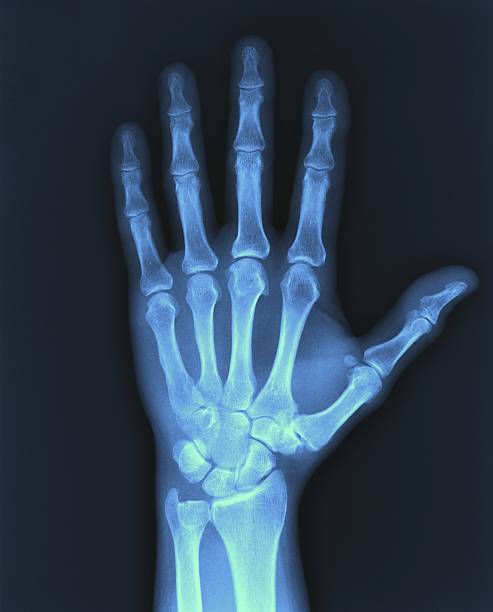

RADIOGRAFÍA DE MANO

La radiografía de mano es un examen de diagnóstico por imagen que emplea rayos X para generar una representación detallada de las estructuras internas de la mano, lo que incluye tejidos blandos, huesos carpianos y las articulaciones de los dedos.

La radiografía de mano es un procedimiento médico utilizado para obtener imágenes precisas de los huesos, articulaciones y tejidos de la mano. Funciona utilizando una máquina de rayos X, la cual emite un haz de radiación que atraviesa el área examinada. Los rayos interactúan de manera diferente con los tejidos, los huesos absorben mayor radiación, lo que los hace aparecer en blanco en la imagen. Los tejidos blandos, por su parte, permiten el paso de los rayos y se muestran en tonos más oscuros.